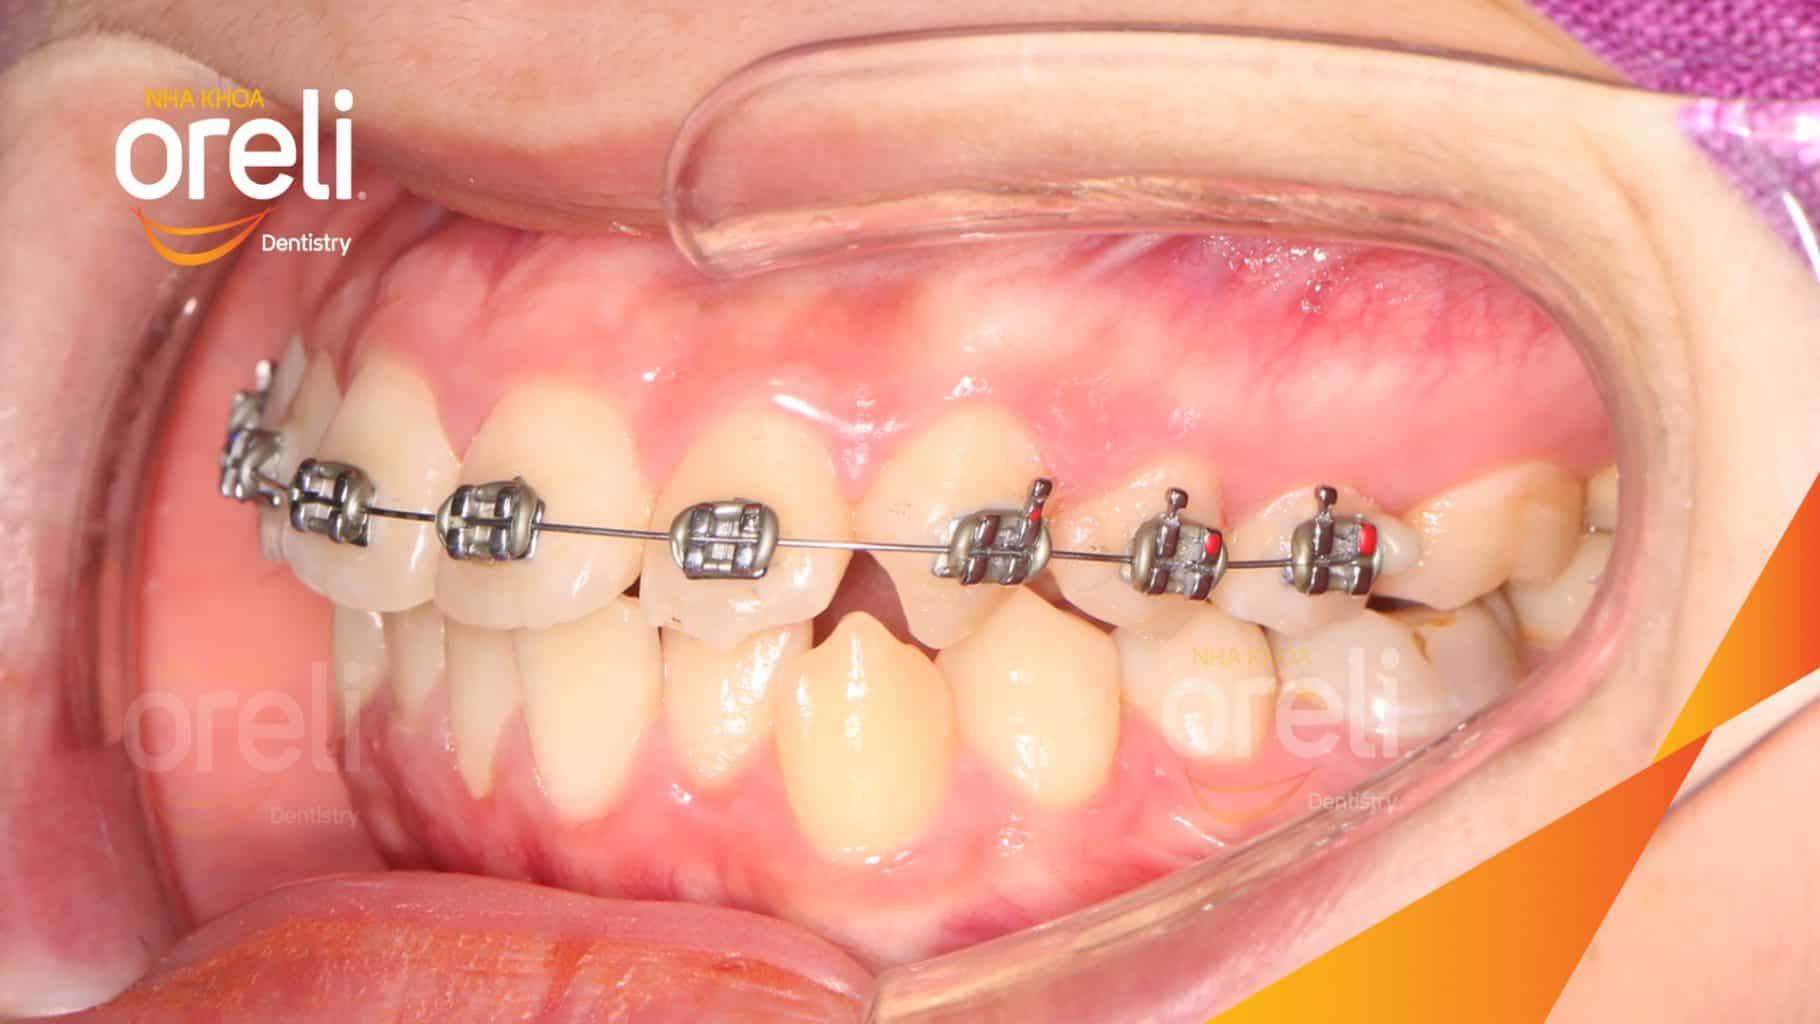

Tình trạng: Nhô xương ổ, trục răng nghiêng trước hai hàm, độ nhô môi nhiều

Giải pháp: Nhổ răng 4 chỉnh hô

Thời gian: 24 tháng

Kết quả: Nụ cười hài hòa, mặt nghiêng đẹp, trục răng cửa đứng